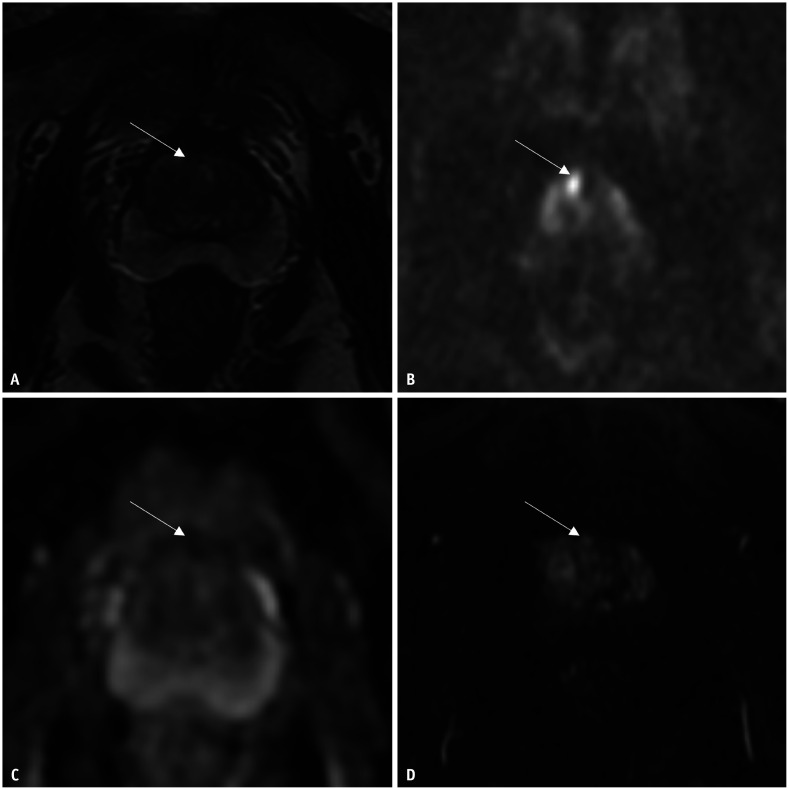

Materials and methods: Clinical and mpMRI data were retrospectively collected from 219 patients with prostate disease between January 2015 and December 2021. All patients underwent systematic prostate biopsy followed by RP. MpMRI included conventional diffusion-weighted and dynamic contrast-enhanced imaging. Multivariable logistic regression analysis was performed to analyze the factors associated with GS upgrading and downgrading after RP. Receiver operating characteristic curve analysis was used to estimate the area under the curve (AUC) to indicate the performance of the multivariable logistic regression models in predicting GS upgrade and downgrade after RP.

Abstract Image